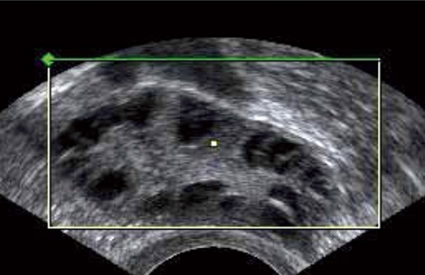

Äggstockarnas utseende bedöms med vaginalt ultraljud. Ett multifollikulärt ovarium med många olikstora folliklar är normalt hos en ung kvinna och ska inte förväxlas med ett polycystiskt ovarium med många likstora antralfolliklar. Kombinerade p-piller kan ofta normalisera ultraljudsbilden. I utredningen ska ingå en värdering av de metabola riskerna, och utgående från denna görs eventuellt oral glukosbelastning.